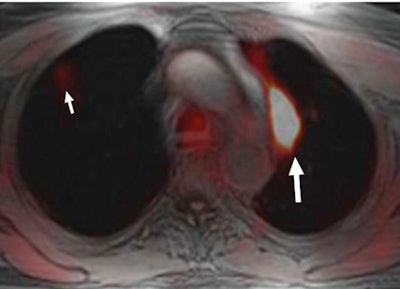

Simultaneous PET/MRI performs better than PET and MRI performed separately for the detection of FDG-avid pulmonary nodules and lesions at least 0.5 cm in size. However, it has problems with non-FDG-avid nodules and smaller lesions, researchers report in the September issue of Radiology.

Simultaneous PET/MRI identified 86 (96%) of 90 FDG-avid pulmonary nodules and 78 (89%) of 88 nodules with a diameter of 0.5 cm or larger, in the study from NYU Langone Medical Center in New York City.

PET/MRI was less proficient in finding lesions smaller than 0.5 cm, achieving a sensitivity of only 38% (19 of 50 nodules), and it had a sensitivity of only 23% (11 of 48) for nodules that were not FDG-avid (Radiology, Vol. 268:3, pp. 874-881).

PET/MRI outperformed MRI alone for all FDG-avid nodules, with a sensitivity of 96% versus 80%, regardless of nodule size, according to the authors.

While the study showed that simultaneous PET/MRI has high sensitivity in the detection of FDG-avid nodules and nodules at least 0.5 cm in size, the combination "has limited sensitivity in the detection of small non-FDG-avid nodules," they concluded. "The clinical importance of these missed nodules is unclear and needs further investigation."